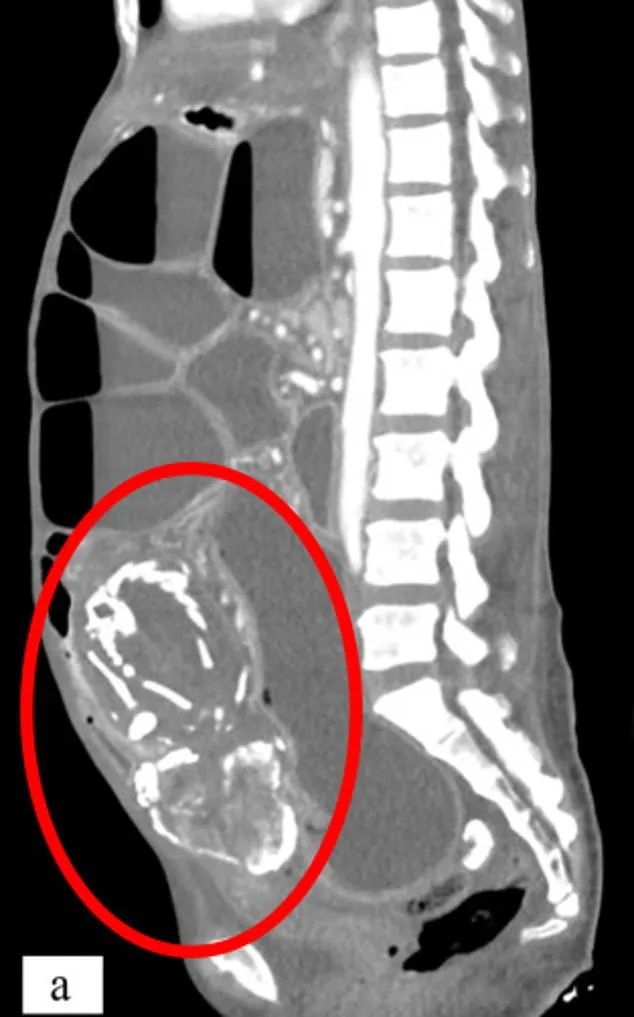

「石胎」導致小腸梗阻、常年消化不良

根據 CT 掃描的發現,她的腹中有一個長15至20cm的石胎,能清晰看到胎兒的骨架。因為石胎體積較大,導致她的小腸梗阻、大靜脈受壓迫、盆骨壓迫、高血壓和感染了幽默螺桿菌、常年消化不良、腹痛。由於鈣化的石胎壓迫大小腸,她一吃多就吐,嚴重的時候吐膽汁,所以不敢多吃,導致營養不良,體質很弱,而她也因為害怕「詛咒」而拒絕了所有口服藥物。